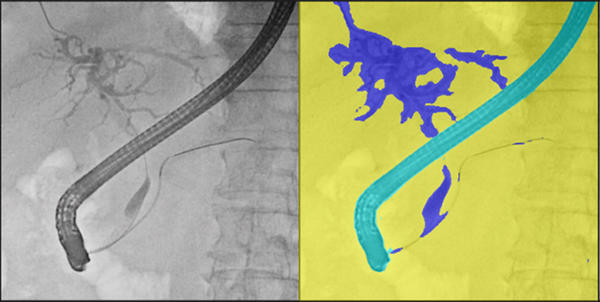

(2)造影剤の使用量低減に貢献する画像処理機能「Boost C*13」

AI技術を活用して開発された造影剤強調処理により,ERCP実施時に造影された胆管領域を検出し,コントラストを強調する。本機能を使用しない透視画像よりも,胆管領域の視認性が向上する。本機能により,1検査あたりの造影剤使用量を低減し,被検者の身体的負担の軽減が期待できる。

胆管領域を検出しコントラストを強調した様子(右画像)